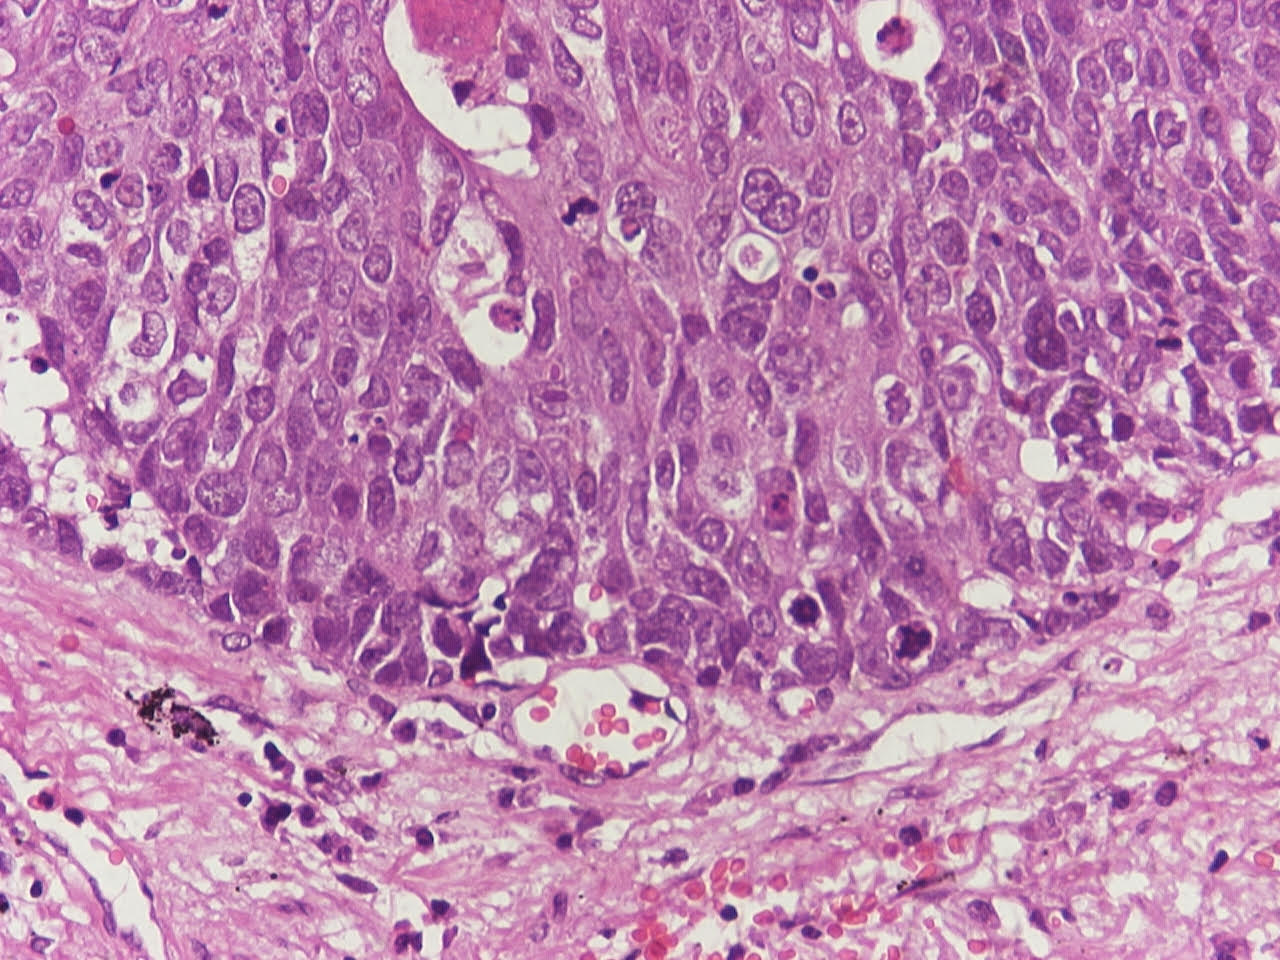

- Neuroendocrine organoid architecture may include nesting with peripheral palisading, anastomosing trabeculae and rosette-like structures (Mod Pathol 2022;35:36)

- > 10 mitoses/2 mm2, extensive / geographic necrosis

- Large cells (~3x size of small cell carcinoma) with abundant amphophilic cytoplasm, intercellular membranes, nuclear pleomorphism, variably coarse, granular or vesicular chromatin with prominent nucleoli (Transl Lung Cancer Res 2020;9:860, Mod Pathol 2022;35:36)

- Occasional rhabdoid features (Pathol Int 2019;69:481, J Cancer Res Ther 2015;11:657)

- Larger tumor cells than atypical carcinoid, high nuclear grade, increased mitotic activity and necrosis (Arch Pathol Lab Med 2010;134:1628)

Microscopic (histologic) images

Contributed by Ioanna Abba Nteka, M.D., Aggeliki Cheva, M.D., Ph.D., Antonia Loukousia, M.D., Roseann Wu, M.D., M.P.H. and Kyriakos Chatzopoulos, M.D., Ph.D.